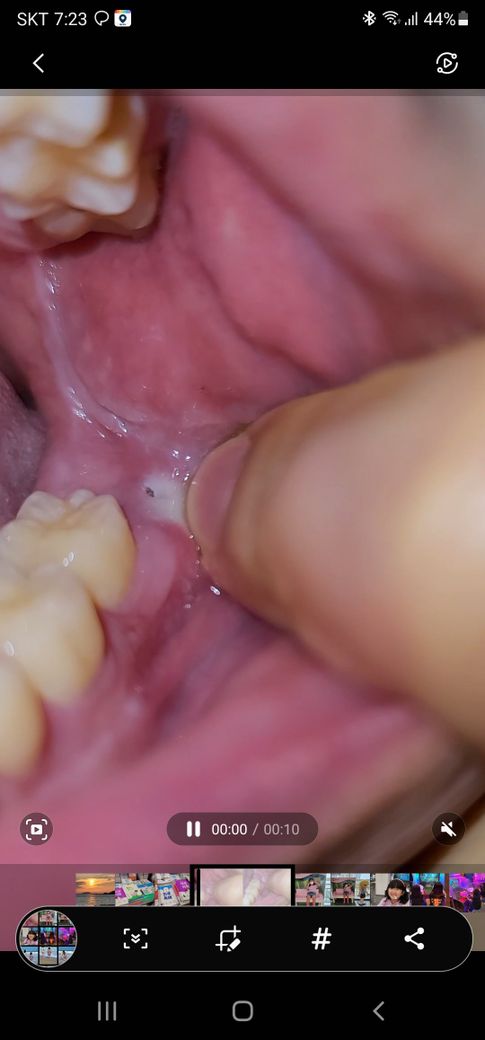

아래. 사랑니부분 검은색구멍?냄새가 납니다

왼쪽아래사랑니 부분. 엽에. 검은색부분이 보입니다

만지면 딱딱하고. 손을가져다가. 냄새를 맡으면

냄새가 나기도합니다

예전치과에서 매복사랑니. 누웠다고 했는데

그것때문에 그런건가요

사진으로봤을때는 구멍난곳이 사랑니가 잇몸을 살짝 뚫고 올라온 부분으로 보입니다.

이 경우, 염증이 생기고 냄새가 날 수 있습니다.

증상이 지속될경우 발치하는것이 좋을 수 있습니다.